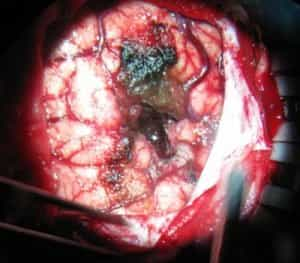

فتح الجمجمة عبر المدخل الجداري القذالي الأيسر مع استئصال الورم.

استغرقت العملية ست ساعات.

التصوير أثناء الجراحة

فتح الجمجمة عبر المدخل الجداري القذالي الأيسر